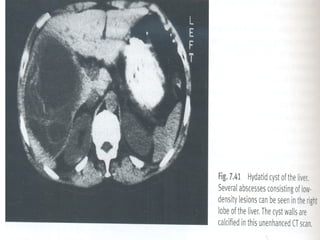

 TAC Abdomen